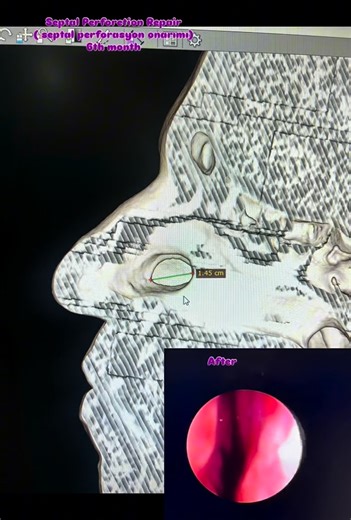

Doç. Dr. Bilal Sizer on Instagram: "Septal perforation repair!!! It has been six months since the septal perforation repair surgery. We are very happy that everything is going well. #septalperforasyononarımı #septalperforation #septalperforation #septumperforasyonu #septumperforation #septumperforasyonuameliyatı #bilalsizerklinik Our clinic is officially authorized by the Turkish Ministry of Health with an International Health Tourism Certificate. All patient photos and videos shared on this pag

Instagram

doc.dr.bilal_sizer

已浏览 4415 次

1 个月前